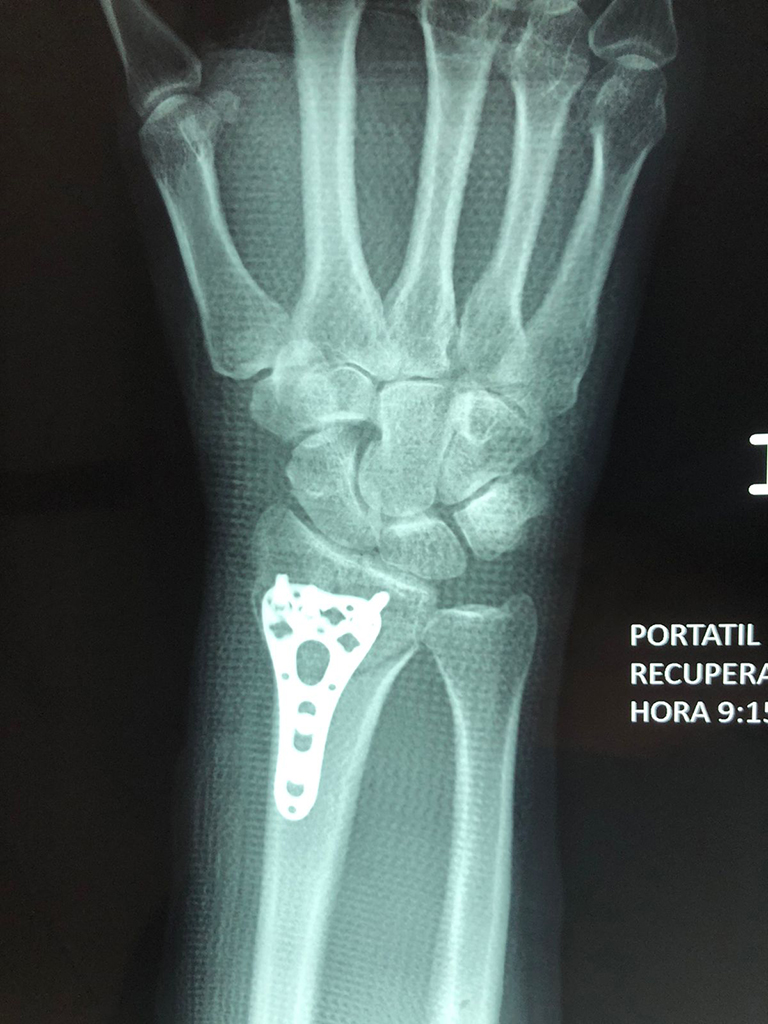

Los procedimientos más comunes en cirugía de la mano son aquellos destinados a reparar traumatismos, incluyendo lesiones de tendones, nervios, vasos sanguíneos, y articulaciones; huesos fracturados; y quemaduras, cortes, y otros daños de la piel.